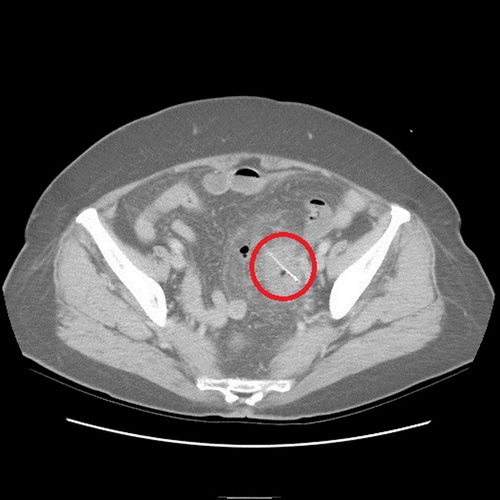

沒想到過了2天,老奶奶又來看診,醫(yī)師便為她安排住院檢查,經(jīng)計(jì)算機(jī)斷層檢查,發(fā)現(xiàn)老奶奶乙狀結(jié)腸部份竟然有根2.5公分的魚刺,且魚刺已經(jīng)穿破腸道,導(dǎo)致橫膈膜下方有氣體出現(xiàn),經(jīng)外科醫(yī)師協(xié)助開刀,終于順利幫老奶奶解決腹部不適的問題。